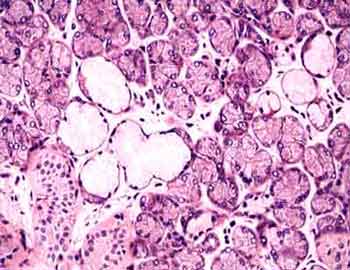

II-4 Párpado (Hematoxilina-eosina) |

Visión

general: Preparación que presenta una sección

del párpado en la que vemos tanto la cobertura externa cutánea

como la mucosa conjuntival interna. Además de ambos tipos de

epitelios, que el alumno debe repasar apoyándose en los conocimientos

ya adquiridos en la Practica I, se ofrece para estudiar anexos cutáneos,

en particular glándulas sudoríparas y sebáceas

en la superficie externa, como las glándulas sebáceas

especiales de Meibomio y las glándulas lacrimales a nivel de

la vertiente interna.

Visión específica: Se observan,

por debajo del epitelio queratinizado, pequeñas glándulas

sudoríparas en grupos como efecto del corte ya que se trata de

formaciones tubulares contorneadas. Junto a ellas mucho mas grandes

y pálidas, generalmente en continuidad con los folículos

pilosos, se pueden poner de manifiesto las glándulas acinares

que por su gradiente madurativo desde la periferia pasan a convertirse

en el centro toda la célula en producto de secreción (holocrínia).

En la cara interna y por debajo de la mucosa conjuntival se observan

grandes unidades sebáceas con un único conducto excretor

(ramificadas), son las glándulas de Meibomio; y finalmente, hacia

el vértice mas interno, un grupo de pequeñas glándulas

mas teñidas y de pequeñas células cúbicas

secretoras de liquido lacrimal.